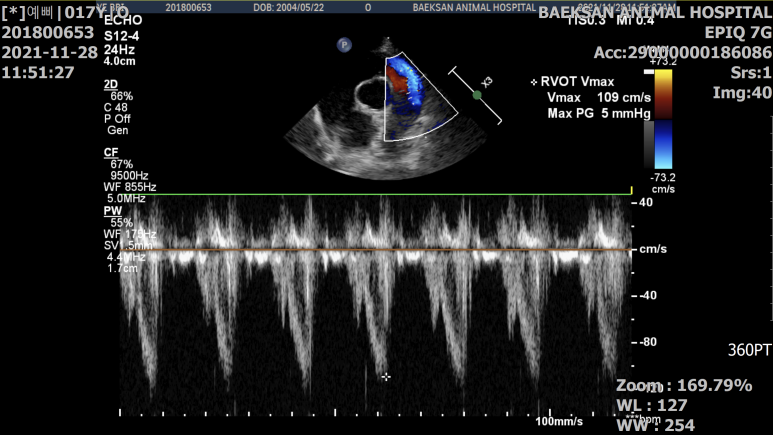

갑기항의 대표적인 합병증으로 고혈압과 비대성심근증(HCM)이 있습니다. 2차적으로 발생하는 질환이지만 이로 인해 다른 증상이 발생할 수 있으므로 조기에 발견하여 관리하는 것이 중요합니다. 예를 들어, 고혈압이 계속되면 망막 박리가 일어나 실명에 이를 수도 있고, 비대성 심근증은 만성화되거나 심장마비 등을 일으킬 수도 있습니다.

또한 엑스레이, 혈액 검사, 소변 검사, 초음파 등의 검사가 필요할 수 있습니다. 갑기항이 유발할 수 있는 합병증을 감별하여 노령묘에 흔히 발병하는 질환이므로 다른 질환에 의해 영향을 받았을 가능성도 배제할 수 없기 때문입니다. 예를 들어 먹는 물의 증가는 갑상선의 증상일지도 모르지만, 당뇨병, 신장병 등의 경우에도 증가할 수 있습니다. 그렇기 때문에 정확한 검사를 통해 진단을 하는 것이 매우 중요합니다.